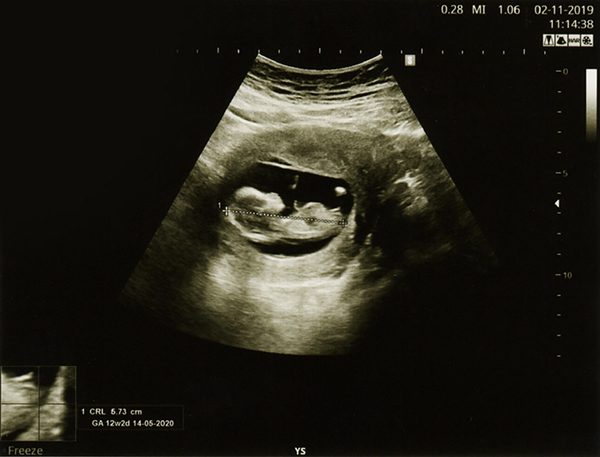

3. Thai kỳ 11-13 tuần 6 ngày

Đây là mốc khám thai quan trọng giúp phát hiện, tầm soát dị tật thai nhi đầu tiên mà bác sĩ khuyến cáo mẹ bầu cần thăm khám đúng lịch.

Bác sĩ Lâm Khoa cho biết, chỉ có khoảng thời gian 11-13 tuần 6 ngày mới có kết quả đo độ mờ da gáy có ý nghĩa, nhờ đó phát hiện được những dị tật bẩm sinh liên quan đến bất thường nhiễm sắc thể như Down, Edward, Patau, và các bất thường hình thái học khác… Ngoài ra, ở lần khám thai này mẹ bầu có thể được chỉ định làm các xét nghiệm máu để tầm soát các bất thường số lượng nhiễm sắc thể thường gặp.

Nếu là lần khám thai này phát hiện có hình ảnh siêu âm bất thường về cấu trúc của thai nhi hoặc nguy cơ bất thường số lượng nhiễm sắc thể cao bác sĩ sẽ khuyến cáo thực hiện các thủ thuật xâm lấn như sinh thiết gai nhau hoặc chọc ối tuỳ theo từng trường hợp để xác định thai nhi có bất thường số lượng nhiễm sắc thể hay không.

“Đây là một xét nghiệm tầm soát cho độ chính xác cao lên đến 99%. Nguy cơ sảy thai do chọc ối hoặc sinh thiết gai nhau là rất thấp, dưới 1% nên mẹ không cần lo lắng”, bác sĩ Lâm Khoa cho biết thêm.